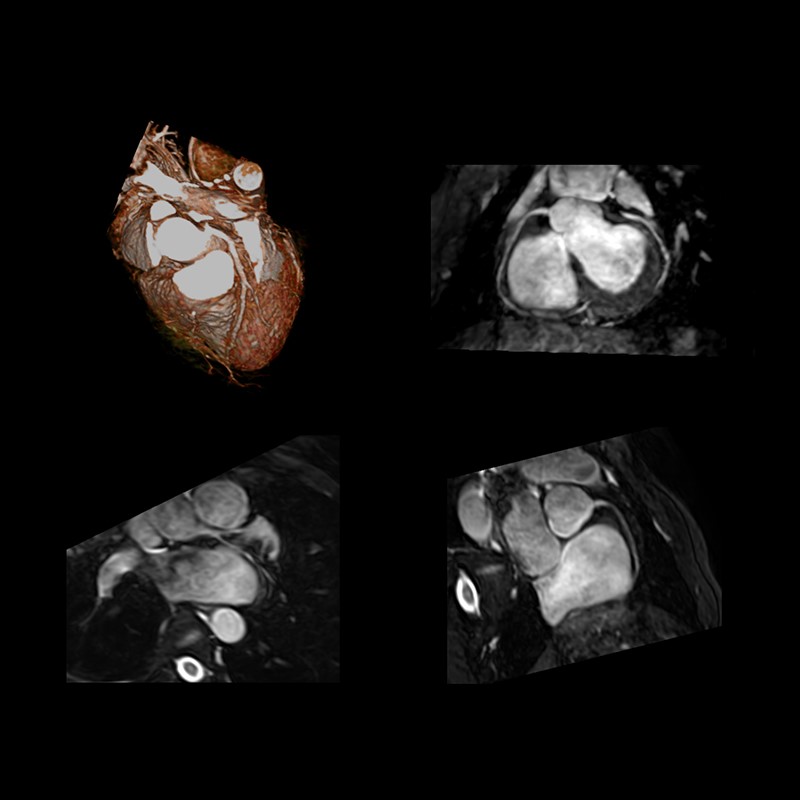

Кардіологія, судинні дослідження